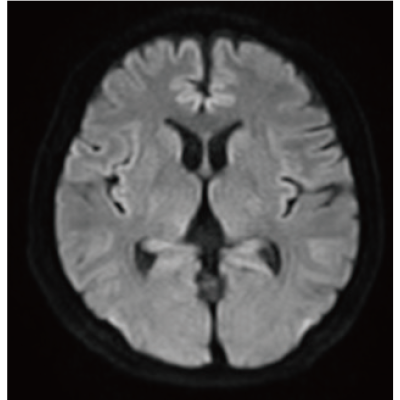

IP-RAPID, que permite um tempo de exame reduzido, mantendo a qualidade da imagem, e DLR Plus, que melhora a qualidade da imagem utilizando a tecnologia Deep Learning*8.

Ao combinar estas duas tecnologias, as imagens de fácil diagnóstico podem ser obtidas com uma velocidade de exame rápida.

O IP-RAPID x DLR Plus também pode encurtar o tempo de aquisição de imagens, permitindo que mais imagens sejam obtidas no mesmo tempo de exame. Imagens adicionais, como diferentes tipos de imagem e seções transversais, podem ser adicionadas ao exame convencional para aumentar a quantidade de informações e tornar o diagnóstico mais fiável.

O IP-RAPID x DLR Plus pode ser usado para exames de imagem básicos, como VolumeScan, RadialScan, HalfScan e muitos outros métodos de imagem, como MultiContrastScan FatSep e DWI.

Também pode ser utilizado com exames demorados, como DWI de corpo inteiro e exames de imagem de toda a coluna, fornecendo informações mais detalhadas em muito mais áreas do que era anteriormente possível.